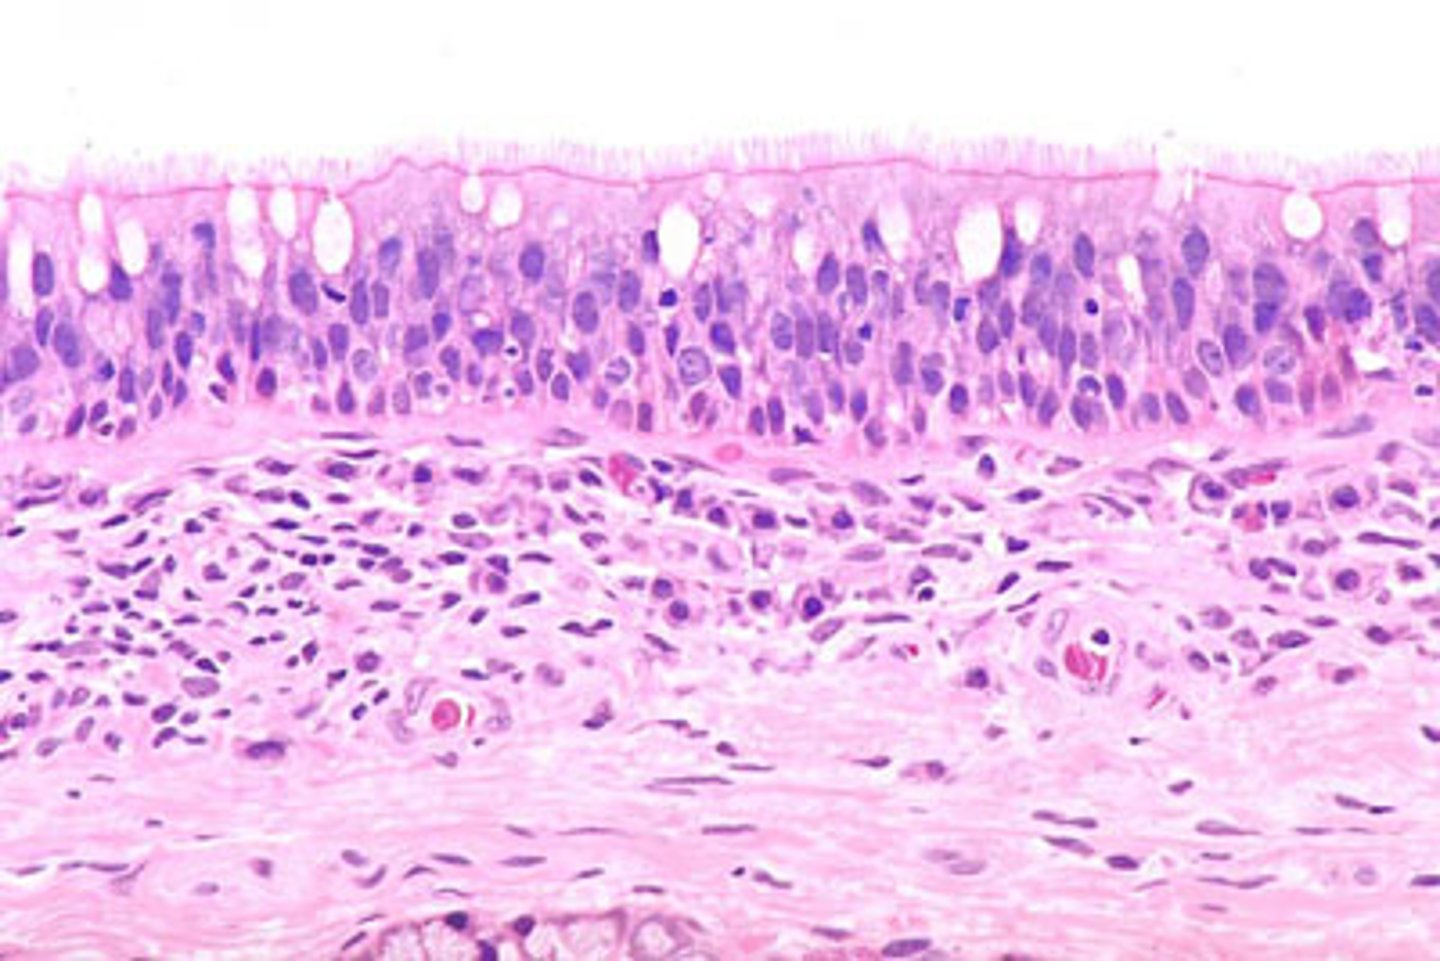

What epithelial transition occurs in the larynx?

Pseudostratified ciliated epithelium -> stratified squamous epithelium (image is at the vestibular folds)

What epithelium lines the true vocal cords? and why is it this specific epithelium?

Stratified squamous non-keratinized epithelium

so we can speak if we had any other lining the voice will be distorted

Understand how the epithelium changes from epiglottis to treachea`

Epiglottis - stratified squamous epithelium with elastic cartilage

False vocal cords - pseudostra. cillated epithelium

True vocal cords - stratified sq. non keratinized epithelium with skeletal muscle

Trachea - pseudostra. ciliated epithelium with goblet cells (respiratory structure)

Describe the transitional epithelium of the larynx

The main transition occurs near the vocal cords, separating the squamous epithelium of the true vocal cords from the respiratory epithelium pseudostratified ciliated